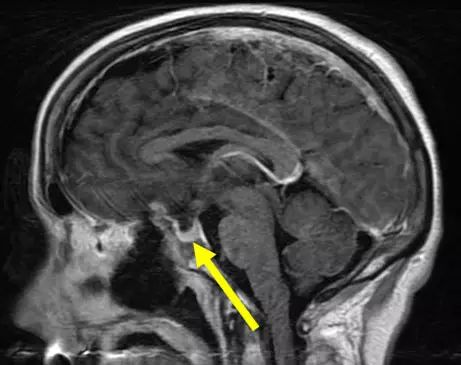

对于表现为脑膜瘤症状的患者,头部CT扫描经常作为较初的影像学检查,但头颅MRI平扫或增强扫描对诊断很有必要。发生在颅颈交界部的脑膜瘤(MRI扫描,矢状位[左]和轴位[右])称为枕...